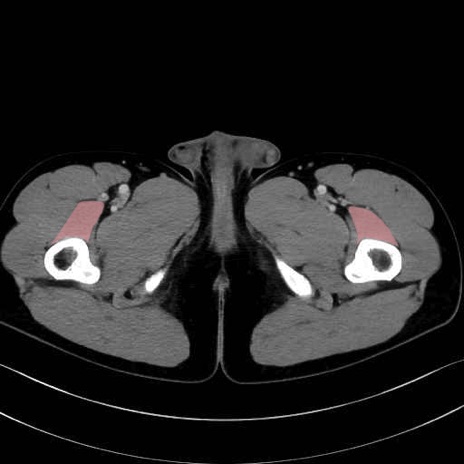

中間広筋 (Vastus intermedius)